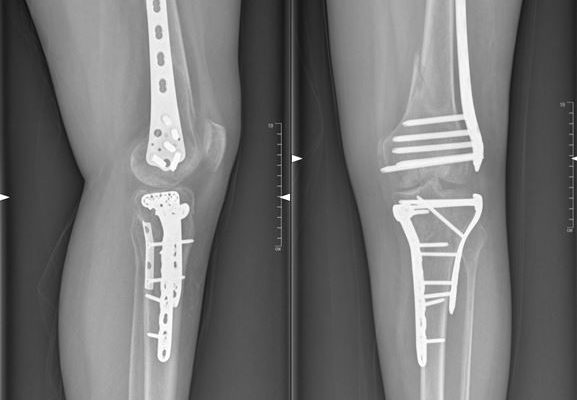

ИИ на страже костей: как искусственный интеллект меняет диагностику переломов В мире, где технологии проникают во все сферы нашей жизни, медицина не остается в стороне.